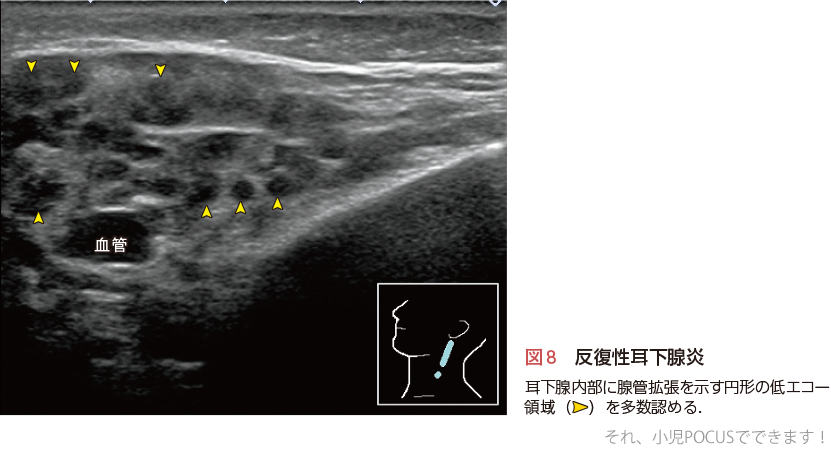

2)反復性耳下腺炎

2〜6歳頃に発症し,年に数回両側または片側の耳下腺の有痛性腫脹をきたす疾患です.多くの症例では10歳頃までに自然治癒します.耳下腺自体の腫大は目立たず,耳下腺内部の腺管拡張が生じるため2〜4 mm程度の円形の低エコー領域が多数認められます(図8).